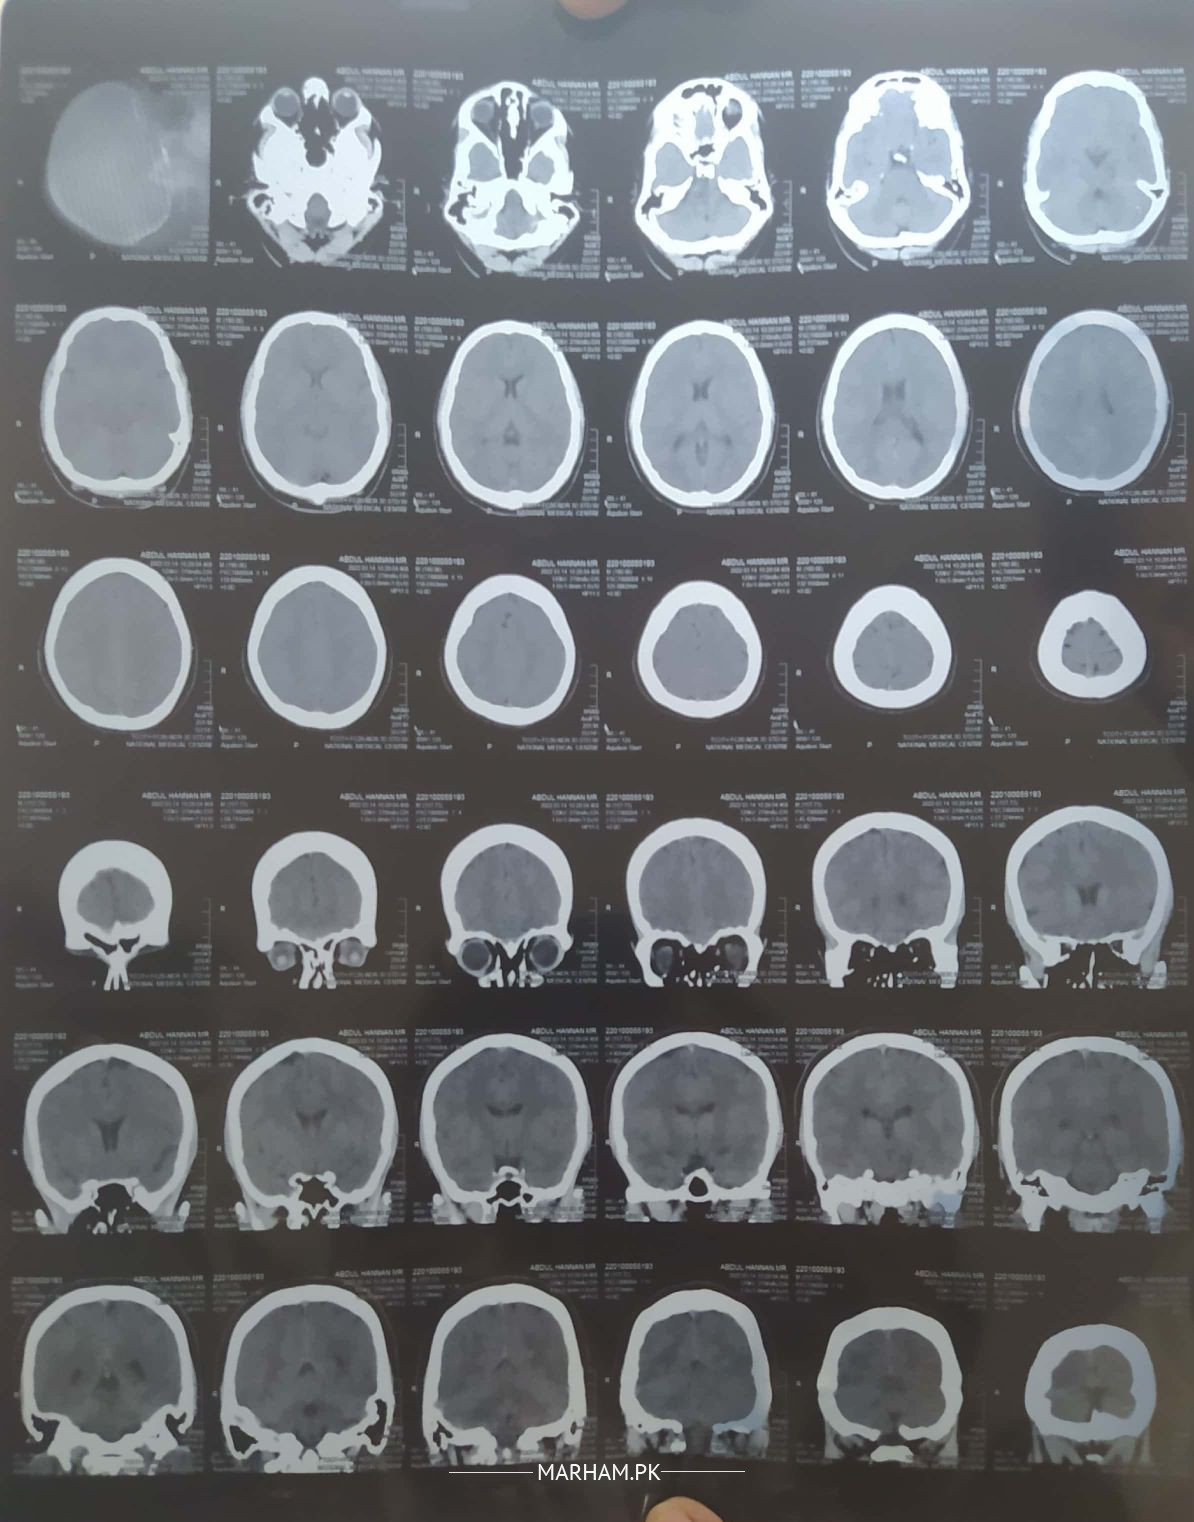

Went to doctor due to memory loss issues and constant headaches. He asked to do CT scan of brain. please review the ct scan, is there anything to worry about or it's normal?

ct looks normal. proper histry and examination needed. get proper chekup from nearby neurologist

normal CT....

ct seems ok

you need to be seen by neurologist or neurosurgeon physically

You need to consult with detailed history. Online consultation at Marham can be arranged but if you need fundoscopy you will need to consult a neurologist face to face

CT scan pe koi pareshani wali baat nahi. aap muaaina karwayain!